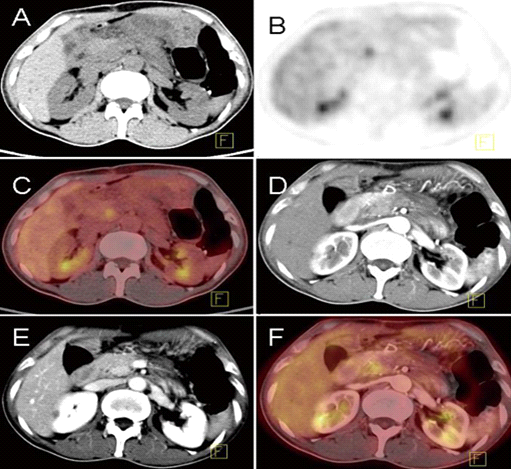

实性假乳头状瘤患者,女性,13岁,左上腹部疼痛不适就诊,增强CT(A-C)检查发现胰腺尾部肿块,平扫表现为密度不均匀,内部见液化坏死区,增强后实质成分动脉期及门脉期渐进性明显强化;PET/CT检查(D、E)肿瘤呈明显高代谢灶,行胰尾部+脾脏切除手术,术后病理切片发现病灶周围胰腺实质浸润及周围血管侵犯,肿瘤细胞丰富(F),未见异型细胞(G),富含泡沫巨噬细胞(H),增值指数Ki 67为4%(I),丰富的肿瘤细胞及高增值指数对应明显FDG高代谢,生物学行为表现周围侵犯及浸润特征。